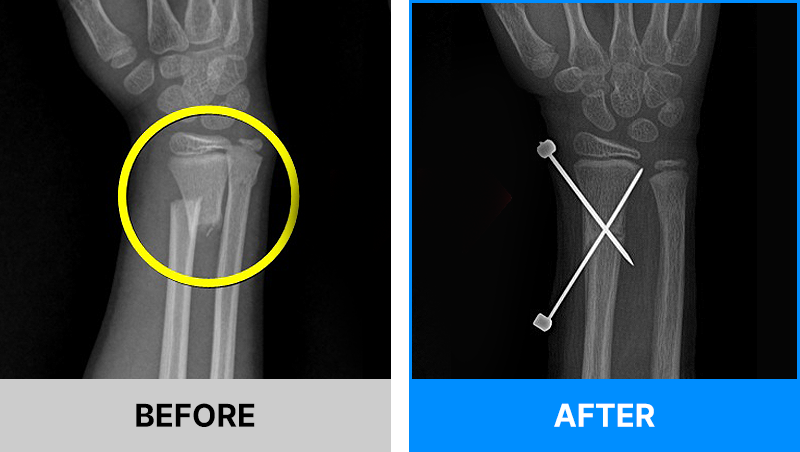

왜 당일 입퇴원 수술일까요?

오래 입원할 필요가 없기 때문입니다.

서울거탑정형외과에서는 전신마취, 척추마취가 아닌

국소부분마취(신경차단) 및 수면 마취를 통해 수술을 시행합니다.

수술 가능 여부 확인은 대표원장과의 진료가 필요합니다.